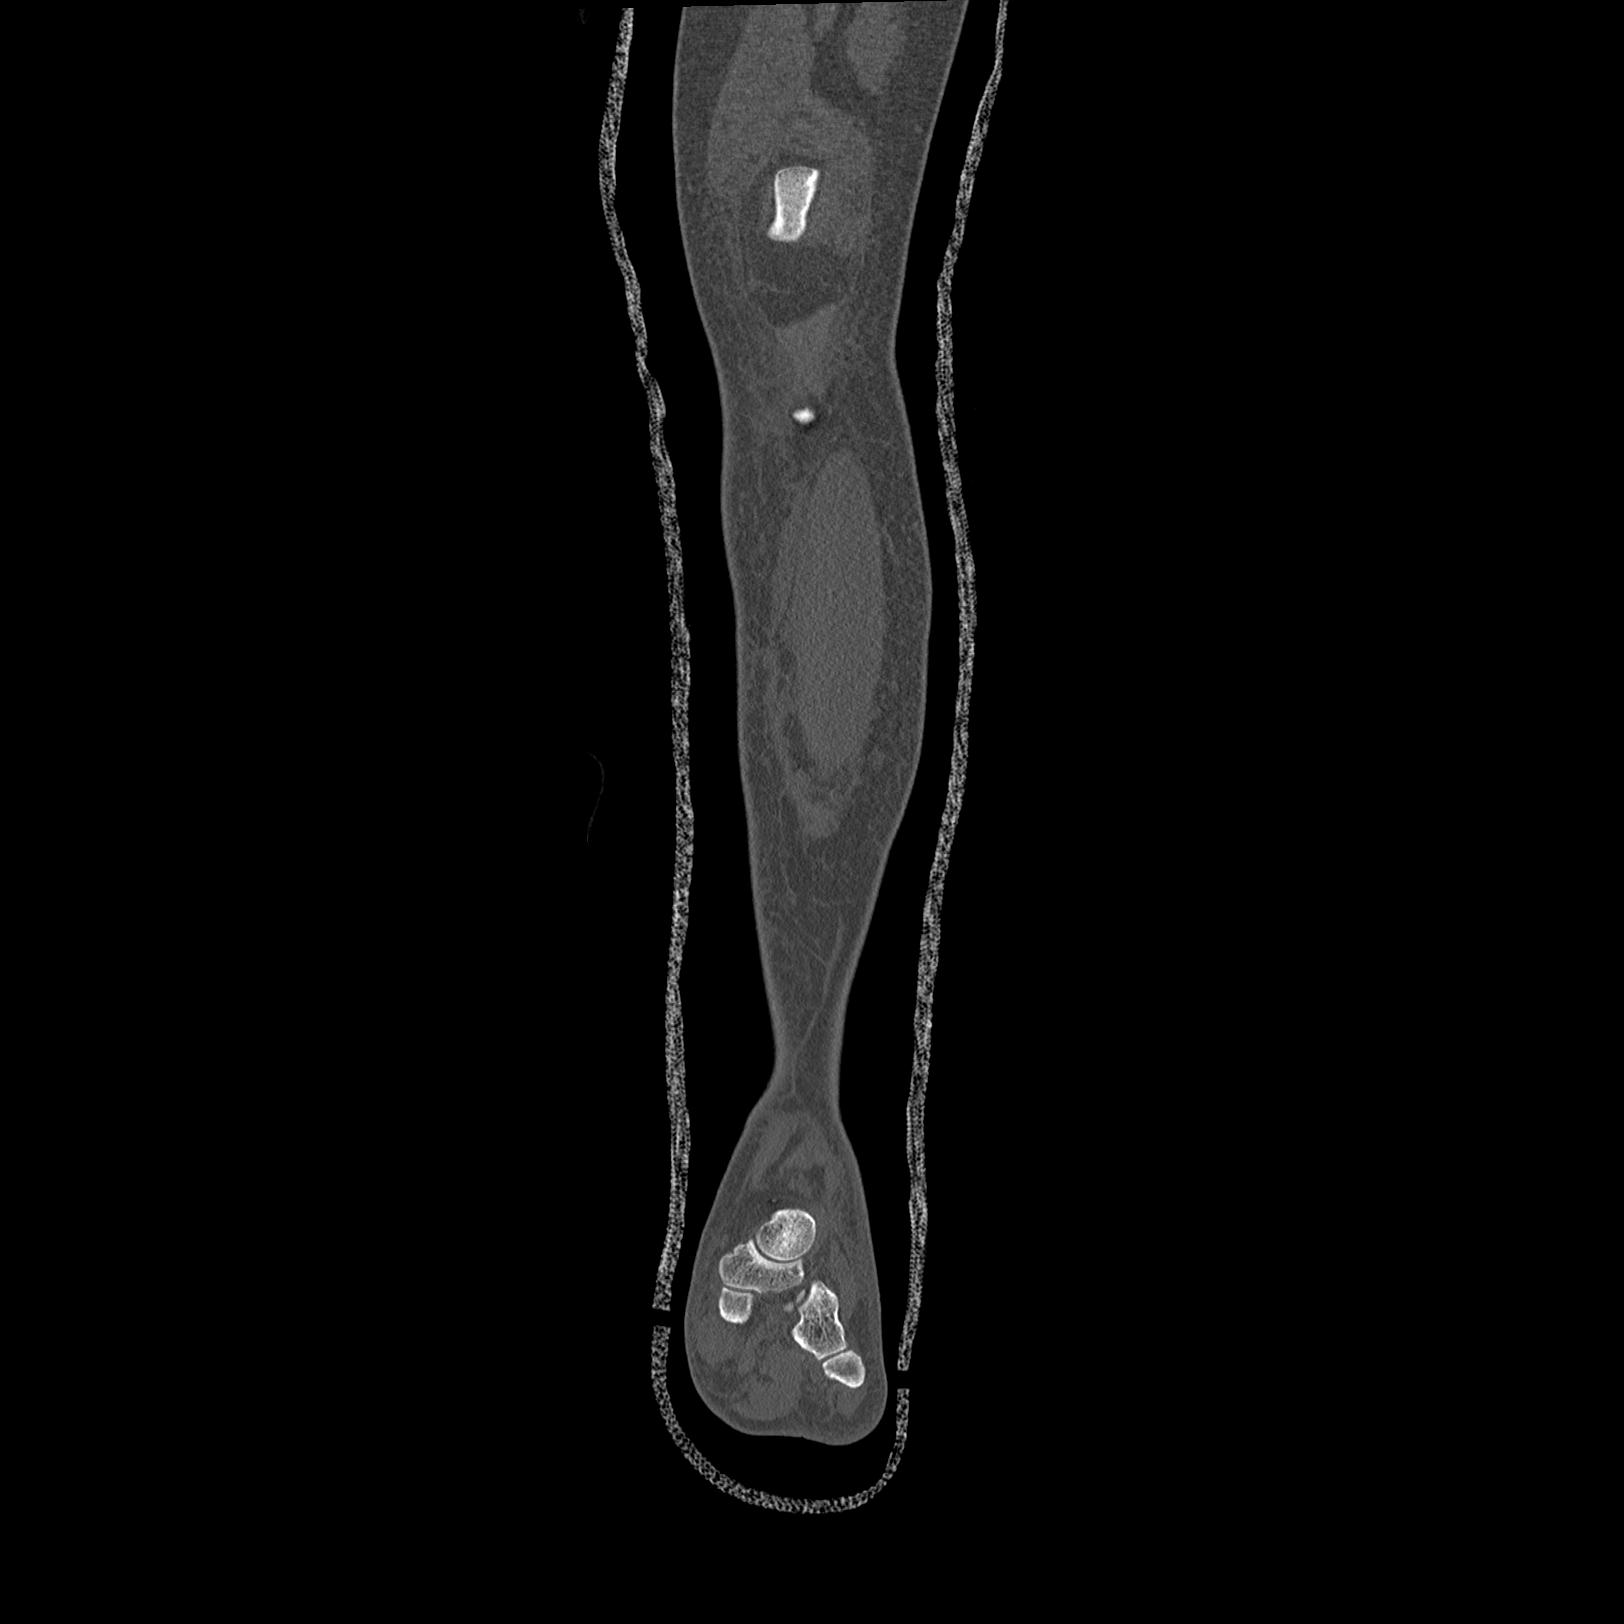

102803 1/12(キウスなし) 1/27 左下腿 4R 30歳女性 左脛骨軸内釘